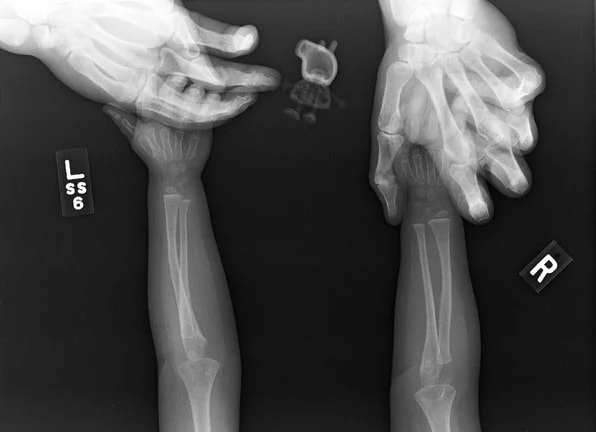

8. Победительницы конкурса «Мисс идеальная осанка»